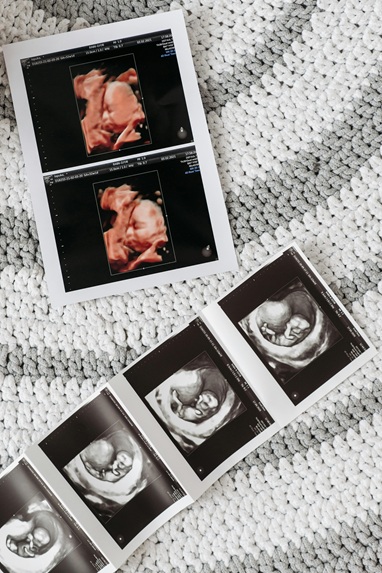

초음파는 대부분의 산모가 받는 표준적인 산전검사로, 태아의 전반적인 성장과 이상 유무를 확인하는 동시에 성별 확인에도 널리 활용됩니다. 성기 구조를 직접적으로 관찰해 판별하는 방식이며, 임신 13~16주 사이부터 가능합니다.

- 13주 전후: 생식기의 윤곽이 형성되기 시작하지만 오차율이 높습니다.

- 16~20주: 성기 구조가 뚜렷해져 정확도가 높아지는 시기입니다.

- 20주 이후: 거의 대부분의 경우 성별 확인이 가능합니다.